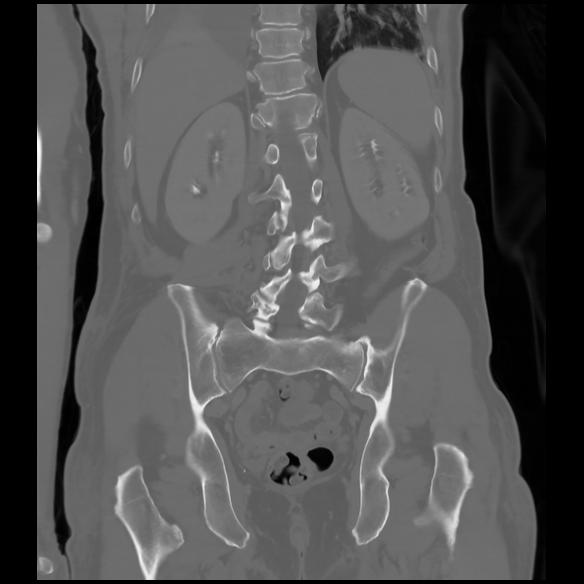

6 CUERPO,CE,Coronal,3.000,CUERPO,Coronal,